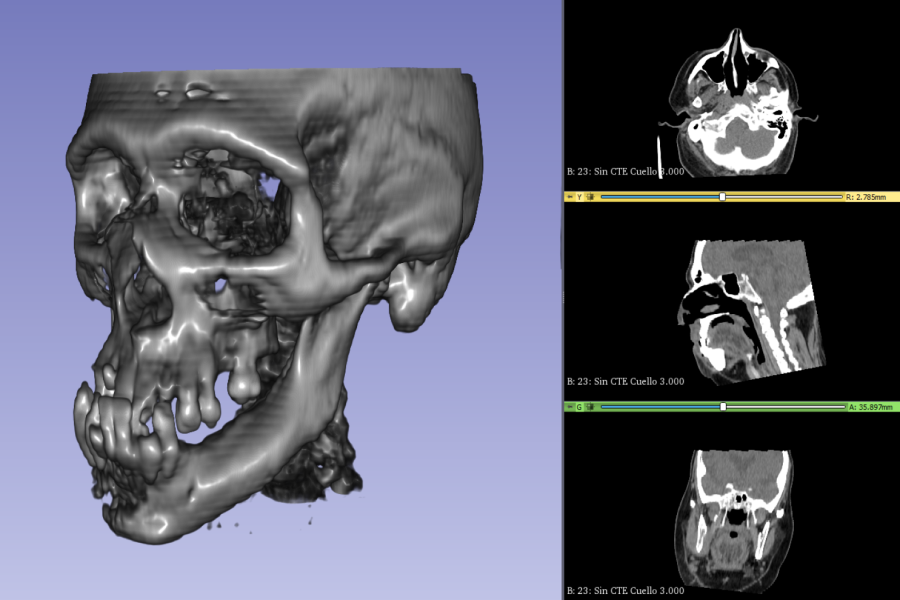

Para la fabricación de modelos para la preparación de una cirugía, lo primero es saber si el tejido es blando o duro. “A partir de esta información, el médico determinará si se usará resonancia magnética y/o tomografía computarizada. Ambas técnicas permiten generar, ya sea desde un campo magnético o rayos X, imágenes 3D sumamente detalladas de órganos y tejidos, lo que permitirá al médico saber con exactitud lo que tiene que sacar y lo que no hay que tocar”, cuenta Joaquín. “Después se lleva a otro software que permite ir moldeando la pieza. Aquí la puedes mover, estirar, crear nuevos volúmenes, hasta crear la reparación virtual para ser aprobada por el médico, quien finalmente dará la confirmación de llevar a imprimir”.

En 2020, LeufüLab presentó en un paper los resultados de una planificación asistida por impresión 3D para la reconstrucción mandibular de uno de sus casos. Aquí, después de dos reconstrucciones quirúrgicas anteriores sin éxito, las que condujeron a dolor, osteomielitis y pérdida severa del hueso mandibular, el trabajo del laboratorio permitió un resultado exitoso.

El hombre de 51 años, paciente del Hospital del Salvador, había sufrido una fractura de mandíbula que derivó en una fístula cutánea submandibular y dejó su mandíbula desviada. La tecnología permitió a los dentistas maxilofaciales mejorar los procesos quirúrgicos, gracias a la planificación, la manufactura personalizada y la impresión 3D que ofrecieron al cirujano múltiples ventajas como reflejar la anatomía del lado no afectado, planificar osteotomías, manipular segmentos óseos, fabricar guías de resección quirúrgica y crear placas de reconstrucción.